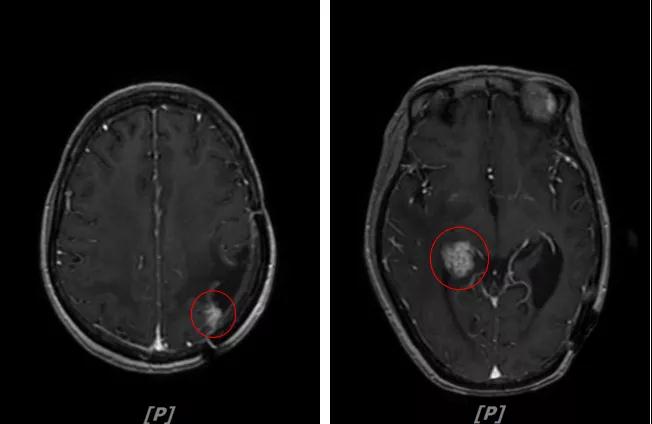

4.病情第3次进展:2018年10月患者头痛症状又加重

头颅增强MR:左侧顶颞叶见片状T1WI低信号、T2WI高信号影,病灶大部信号接近脑脊液;增强后可见左侧额叶、顶叶、两侧海马及右侧小脑半球呈多发斑点状、结节样明显强化,大者大小约14x11mm,较2016-12-11增强老片病灶增大、增多;两侧半卵圆区、侧脑室旁见较对称片状T1WI低信号、T2WI高信号影,增强后未见明显强化( 较2017-8-9MR老片稍明显) ;余脑室、脑池、脑沟大小形态可,中线结构居中无移位。左侧上颌窦粘膜轻度增厚

左顶颞叶转移瘤治疗后改变;脑内多发强化灶,考虑转移,较前增大增多

两侧脑室旁云絮状异常信号:考虑放疗后改变

患者二线治疗的PFS为22个月,2018年11月患者给予后续解救治疗为吡咯替尼(400mg/d)联合阿那曲唑;患者头痛症状好转,病灶继续缩小,继续定期复查。